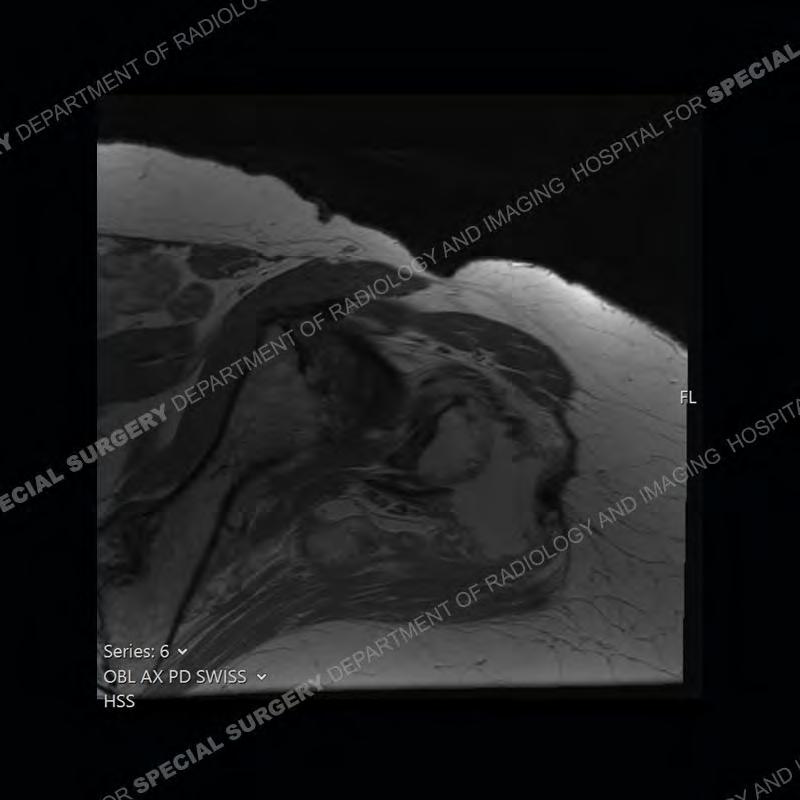

The radiograph is not particularly contributory in this case. The MRI demonstrates markedly abnormal architecture of the gluteus minimus and anterolateral band of the gluteus medius. Portions of the tendons are high signal, portions are highly attenuated, and portions are disrupted. A large, complex fluid collection is present in the adjacent soft tissue.

Diagnosis: Gluteal Tendinosis and Disruption with Complex Trochanteric Bursal Collection

Not as much of a diagnostic dilemma as many of the other cases shown but just a nice example of the pathology seen of the gluteal tendons and a cause of trochanteric pain. Although, frequently thought of in isolation, trochanteric bursitis or bursal thickening is much more commonly a reactive change to underlying pathology of the subjacent gluteal tendons. The gluteus medius is divided into a posterior band and an anterolateral band. Tendinosis and partial tearing very commonly will involve the gluteus minimus and especially the more posterior fibers and then propagate into the anterior lateral band of the gluteus medius. Involvement of the posterior band of the medius is much less common and engenders a marked degree of functional impairment.

The bursae about the greater trochanter can be a little bit confusing especially given the terminology. Trochanteric bursitis is implied to mean the subgluteus maximus bursa which is present deep to the maximus and just lateral/superficial to the trochanter. That is the bursa involved in this case. In this case the complexity of the bursa relates to the tendon tearing with inflammatory change and probably hemorrhage accounting for the complexity. Two other, less frequently involved bursa are also present. The subgluteus medius and subgluteus minimus bursa are found just deep to the named tendons. Although pathology does frequently follow the previously described pattern it is possible to have isolated pathology to either the medius or minimus.